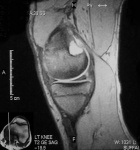

D.O. - 14 year old male with one year hx of left knee pain.

Zoom image: Radiological image Radiological image.